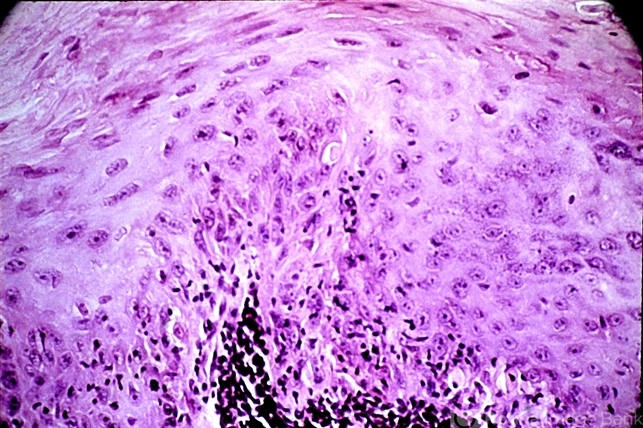

- epidermal cells, dysplasia, epithelium, dyskeratosis

- Loss of orderly maturation of epidermal cells (dysplasia). The red blood cell-like ellipse in the center of the epithelium is a cell which has keratinized out of place (dyskeratosis).